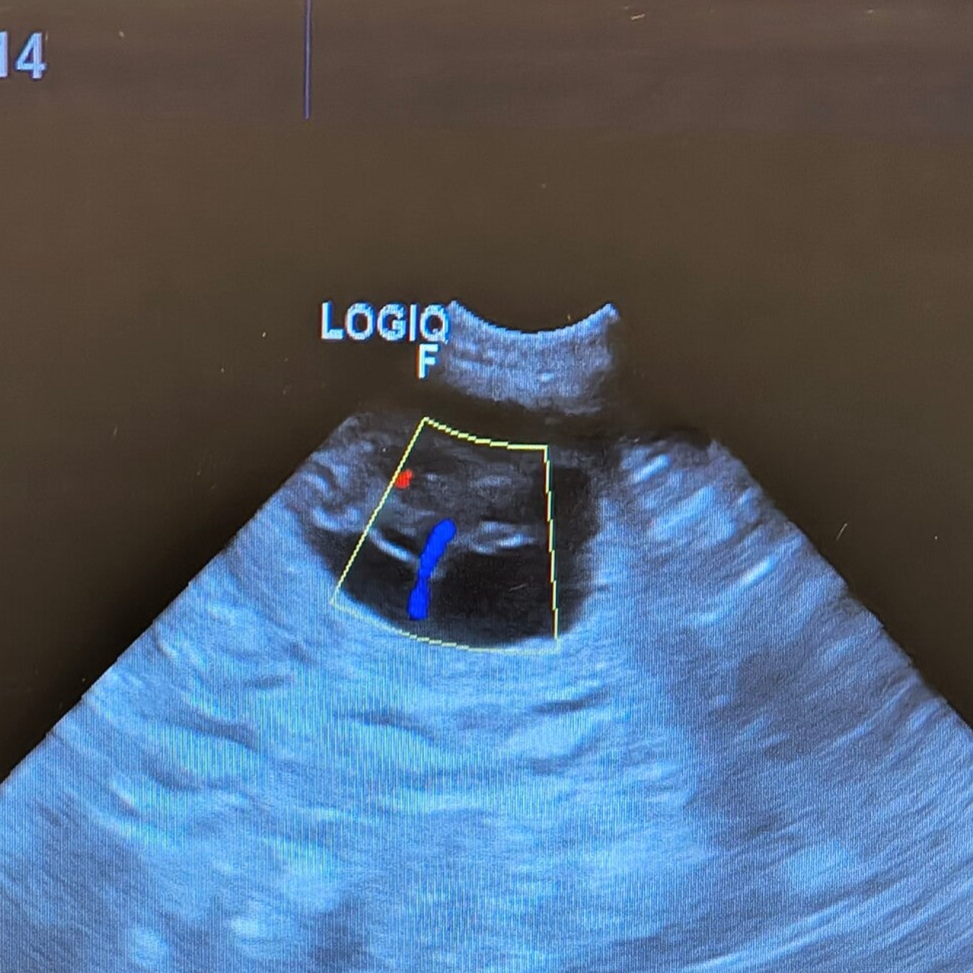

Der Ultraschall war positiv